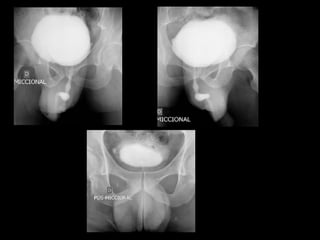

Refluxo da bexiga para trato urinário superior

Anormalidade de maturação da junção vesicoureteral

Pode estar associada a outras anomalias, como válvula de

uretra posterior ou duplicação completa do trato urinário

Mecanismo valvular

UCG: graduação do refluxo

Vesicoureteral Reflux and Reflux Nephropathy

Willian Carlos Nahas, Anuar Ibrahim Mitre, Sami Arap, Gilberto Menezes de Góes

Fernbach et al. RadioGraphics 2000; 20:155–168.

Refluxo 1º: O retorno de urina da bexiga para o uréter, conseqüência de uma

anomalia congênita da junção ureterovesical.

Hipoplasia de musculatura trigonal associada à diminuição do comprimento

do ureter submucoso

Refluxo 2º: é conseqüente à patologia obstrutiva intravesical, à disfunção

neuromuscular da bexiga ou outras anomalias, como válvula da uretra

posterior e ITU

Refluxo Ativo:o refluxo durante a micção

Refluxo Passivo: presente na fase de enchimento vesical

Refluxo vesicoureteral, Projeto Diretrizes, 2006.

Fernbach et al. RadioGraphics 2000; 20:155–168